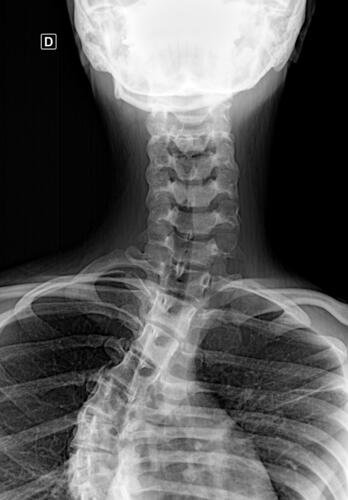

A Vá tem 13 anos e precisa urgentemente realizar uma cirurgia na coluna.Valentina foi surpreendida com o diagnóstico de escoliose hepática grave com 67 graus de desvio (desvio longitudinal da coluna), e precisa realizar com urgência a cirurgia corretiva, os exames foram realizados em Porto Alegre, mas a cirurgia está marcada para dia 13/07 em São Paulo devido a gravidade do caso, para isso a família terá que ficar residindo próximo ao hospital em São Paulo por no mínimo 30 dias para uma plena recuperação. Sabemos bem que qualquer procedimento cirúrgico é delicado, na coluna então nem se fala.Após o diagnóstico e o prognostico dessa doença a família se desfez de alguns bens (carro e moto) para cumprir os prazos dos exames e consultas, necessitando agora arrecadar o valor para a estadia da pequena Valentina e seu pós operatório (medicação, consultas e fisioterapia).

Em anexo os exames (laudo e imagens) para expressas a gravidade do caso.